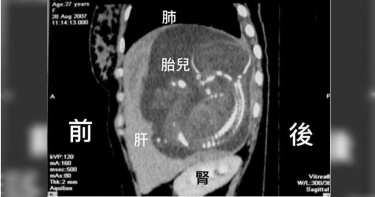

全球僅31例!以為子宮外孕切除輸卵管 胎兒竟是「長在肝臟裡」

ICU重症醫師陳志金今天於臉書分享一篇文章,文中敘述一開始朋友傳此篇文章給他看時,他還以為是假新聞,因為子宮外孕怎麼可能發生在肝臟?而且胎兒竟然在肝臟裡生長到20多周,實在超乎他的想像。誰也想不到子宮外孕竟然發生在肝臟,最後因為腹腔大量出血,母子均不幸身亡。(圖/翻攝自《ICU醫師陳志金》粉絲頁)沒想到竟然是真的!陳志金表示此篇文章來自一位越南醫師2007年的部落格貼文,文中描述這是一位27歲的女性,她因為出現腹腔出血,而懷疑是輸卵管子宮外孕,這也是子宮外孕最常發生的位置,占約97%,醫師因此切除了該名女性右側輸卵管,但是卻沒有在輸卵管上發現胚胎。兩個月後,這名女子再度經歷腹腔內出血,這次才驚訝發現胎兒其實是長在肝臟裡面!而且已經懷孕23周了!雖然經過緊急手術,仍因為大量出血,胎兒和母親都沒辦法活下來。撰寫文章的越南醫師文中表示,該名女子第一次檢查時,醫師僅做「經陰道超音波」,而沒有做「腹部超音波」,因此才會無法發現肝臟內居然有胎兒!不過,誰也無法想像子宮外孕會發生在肝臟,越南醫師表示當時全世界僅報告4例,後來作者於2018年又再次回顧全世界發生的31利!陳志金醫師也提醒,子宮外孕最危險之處就是大量出血而危及性命,女性若發生當月經沒來、有異於月經的陰道出血,再加上腹痛,就要提高警覺!在輸卵管或任何臟器破裂以前,有些患者甚至不會有腹痛,所以不正常的出血都要小心。